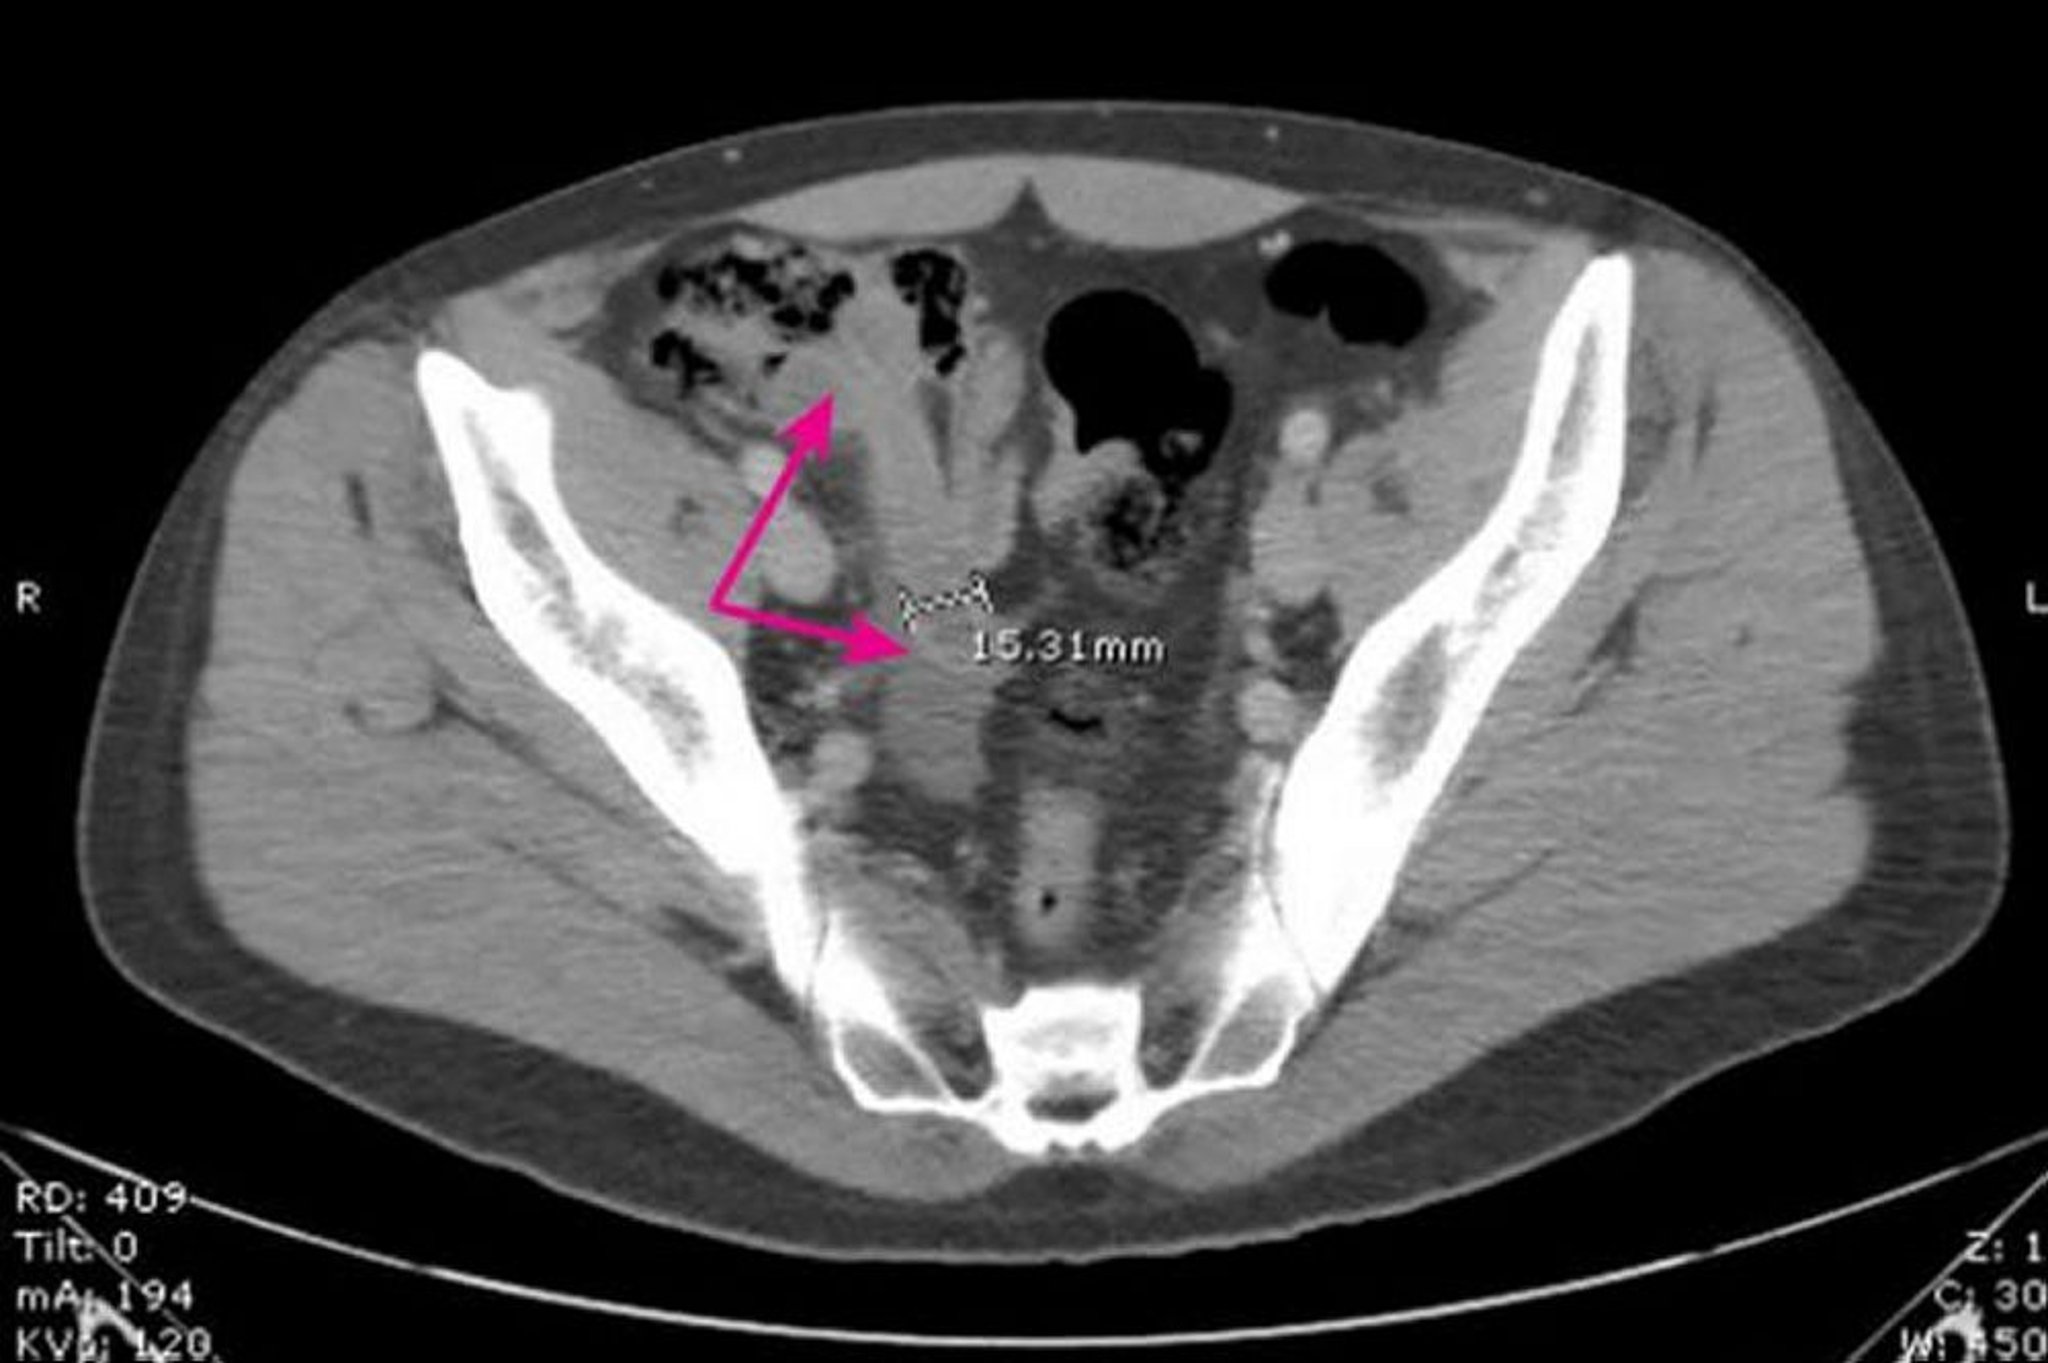

Esta imagen muestra un apéndice dilatado, de paredes gruesas (flechas) que miden 15,31 mm de diámetro y presenta cambios inflamatorios circundantes.

Image provided by Parswa Ansari, MD.